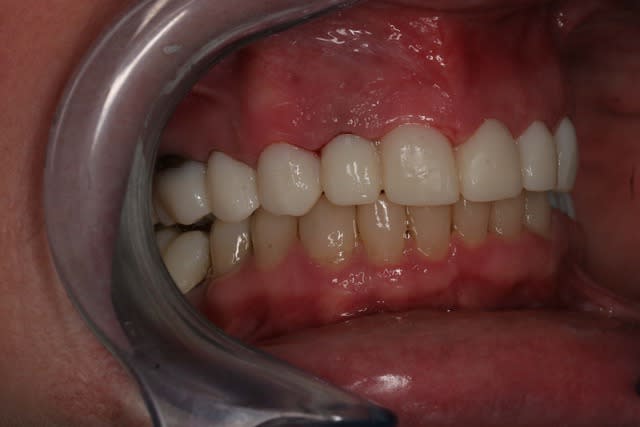

Et voila la pose , pour les habitants du nouveau monde c'est très coloré, pour les Franchouillard c'est naturel... perso je m'en fout la patiente est toute joilleuse et j'ai pas honte de moi, j'ferais encore mieux dés qu'on m'en donneras l'occasion.

Fin 002 j3hb61 - Eugenol

Fin 005 htq1ba - Eugenol

Fin 006 dpgjbp - Eugenol

Fin 008 owjdyz - Eugenol

Fin 007 lhlszz - Eugenol